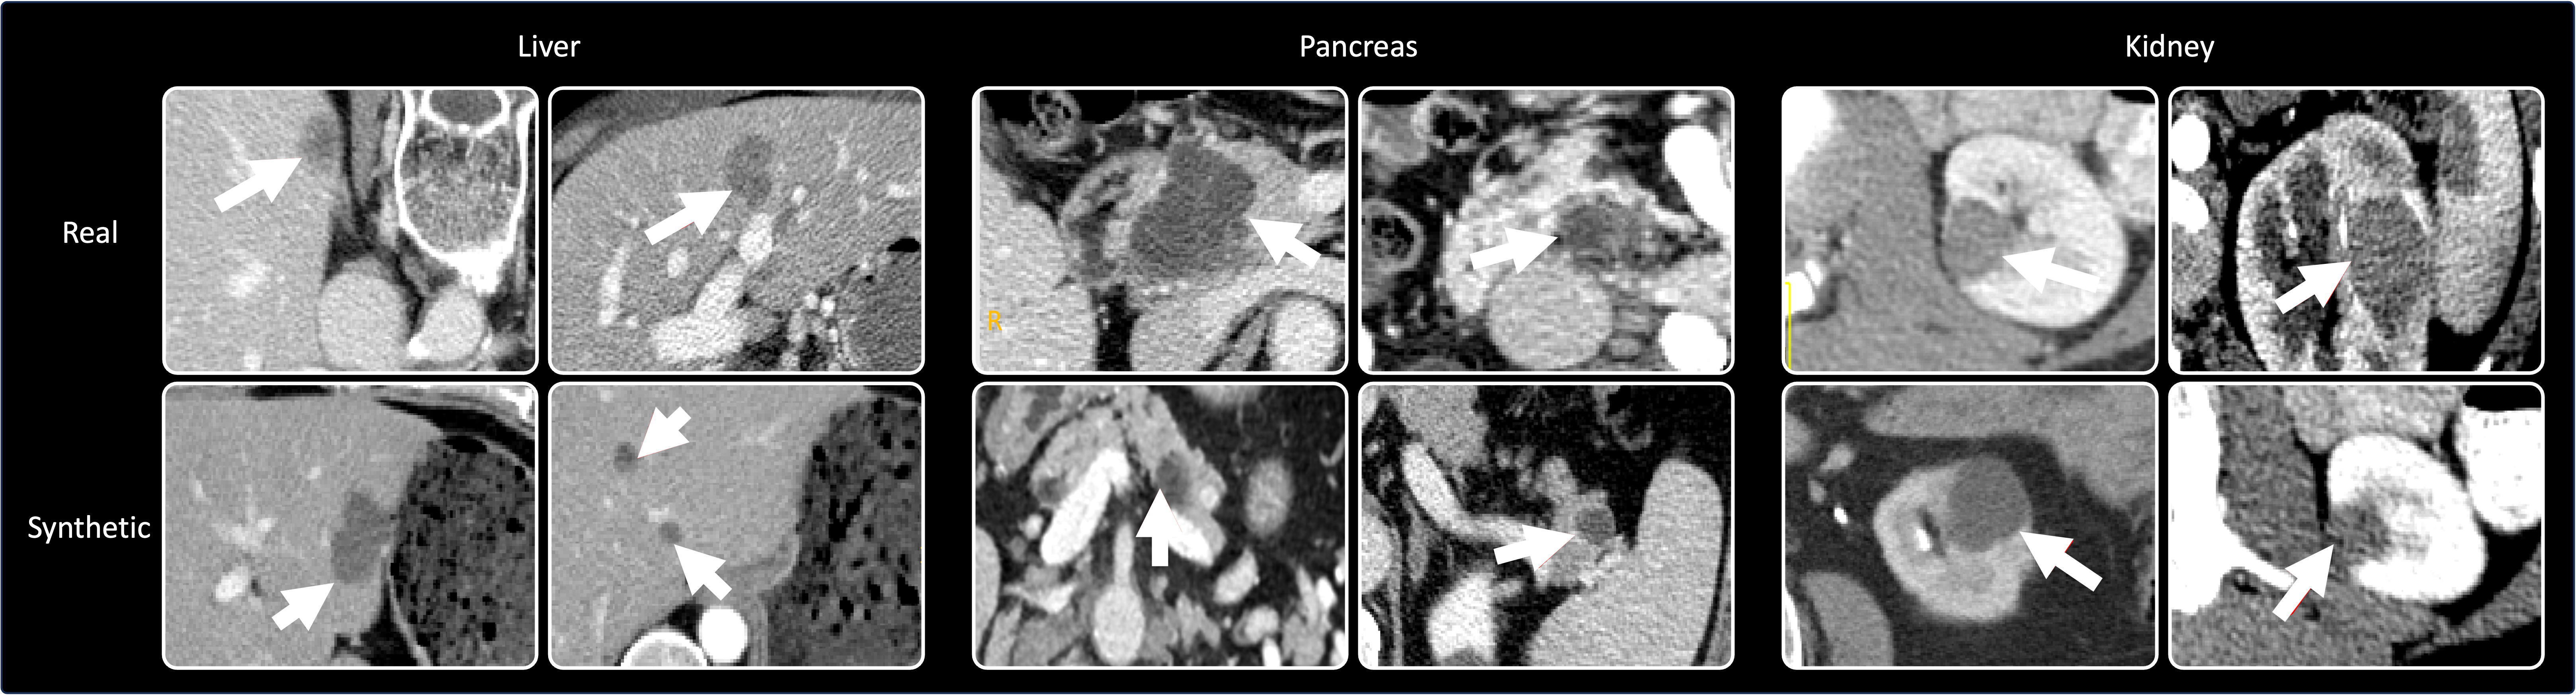

Refer to caption

Figure 7: Examples of synthetic tumors generated by DiffTumor chen2024towards on the liver, pancreas, and kidney.

Diffusion Models ozbey2023unsupervised ; khader2023denoising provide more stable and reliable training compared to GANs, as they gradually denoise data, making the optimization process easier to control. Additionally, Diffusion Models are capable of generating high-quality, diverse samples with fewer issues related to mode collapse. DiffTumor chen2024towards is the first to explore tumor synthesis in abdominal organs using Diffusion Models and demonstrates an efficient method for achieving generalizable tumor synthesis (Fig. 8). Tumors generated by DiffTumor are illustrated in Fig. 7.

Figure 8: Overview of DiffTumor framework. In pursuit of achieving generalizable tumor synthesis, DiffTumor encompasses three stages. ① The first stage is the training of an Autoencoder Model—comprising an encoder and a decoder—to learn comprehensive latent features. The learning objective in this stage entails image reconstruction conducted on 9,262 unlabeled three-dimensional CT volumes. Both the trained encoder and decoder are integral to subsequent stages. ② The second stage involves training a Diffusion Model—a specialized generative model—by utilizing latent features and tumor masks as conditions. Once trained, the model is capable of generating the requisite latent features for the reconstruction of CT volumes with tumors, utilizing arbitrary masks. ③ The third stage entails training a Segmentation Model with CT volumes of synthetic tumors, reconstructed by the decoder. Armed with a considerable repository of healthy CT volumes, DiffTumor has the capacity to generate an extensive collection of synthetic tumors, which vary in location, size, shape, texture, and intensity, thus contributing to the enhancement of AI models for tumor detection and segmentation.